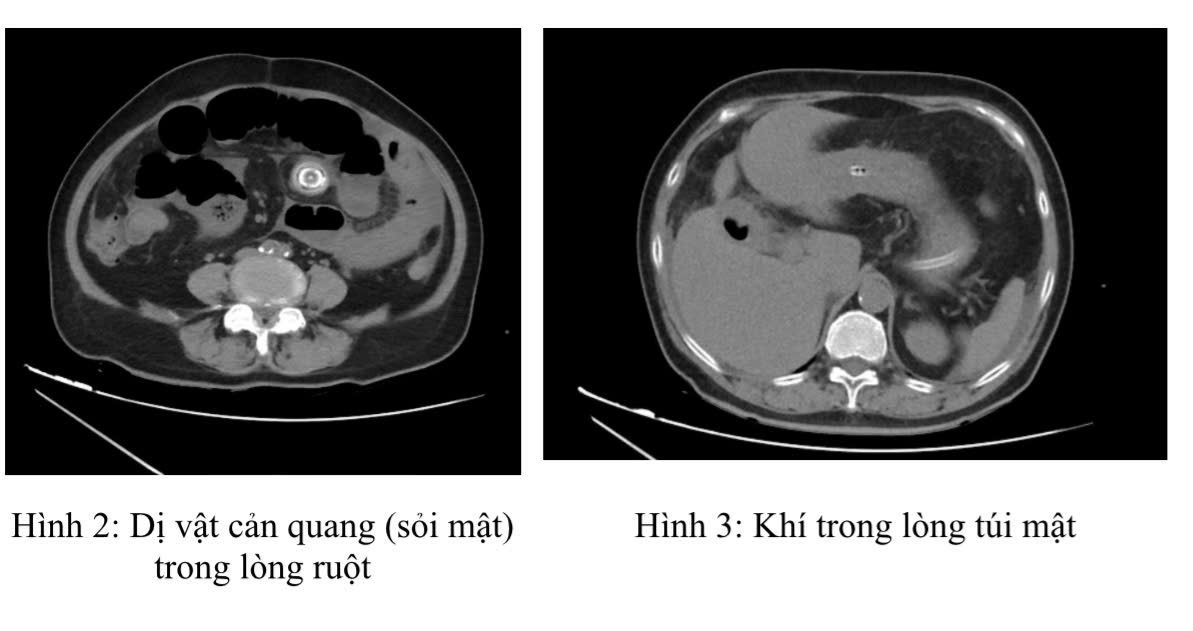

Ngay lập tức, các bác sĩ của Trung tâm Phẫu thuật Tiêu hóa đã tiến hành các thăm dò cần thiết. Kết quả X-quang bụng không chuẩn bị cho thấy dấu hiệu các quai ruột giãn hơi. Chụp cắt lớp vi tính ổ bụng (CT scan) đã xác định rõ ràng tình trạng tắc ruột. Hình ảnh CT cho thấy giãn các quai ruột non quanh rốn kích thước 36mm có mức dịch khí, vị trí chuyển tiếp có dị vật cản quang hình tròn kích thước 23mm. Đồng thời, túi mật thành dày nhẹ, chứa khí có đường thông với tá tràng. Đây chính là “bộ ba dấu hiệu Rigler” điển hình của tắc ruột do sỏi mật, bao gồm: hình ảnh khí trong đường mật (pneumobilia); tắc ruột non với mức nước-khí; và hình ảnh sỏi mật lạc chỗ trong lòng ruột.